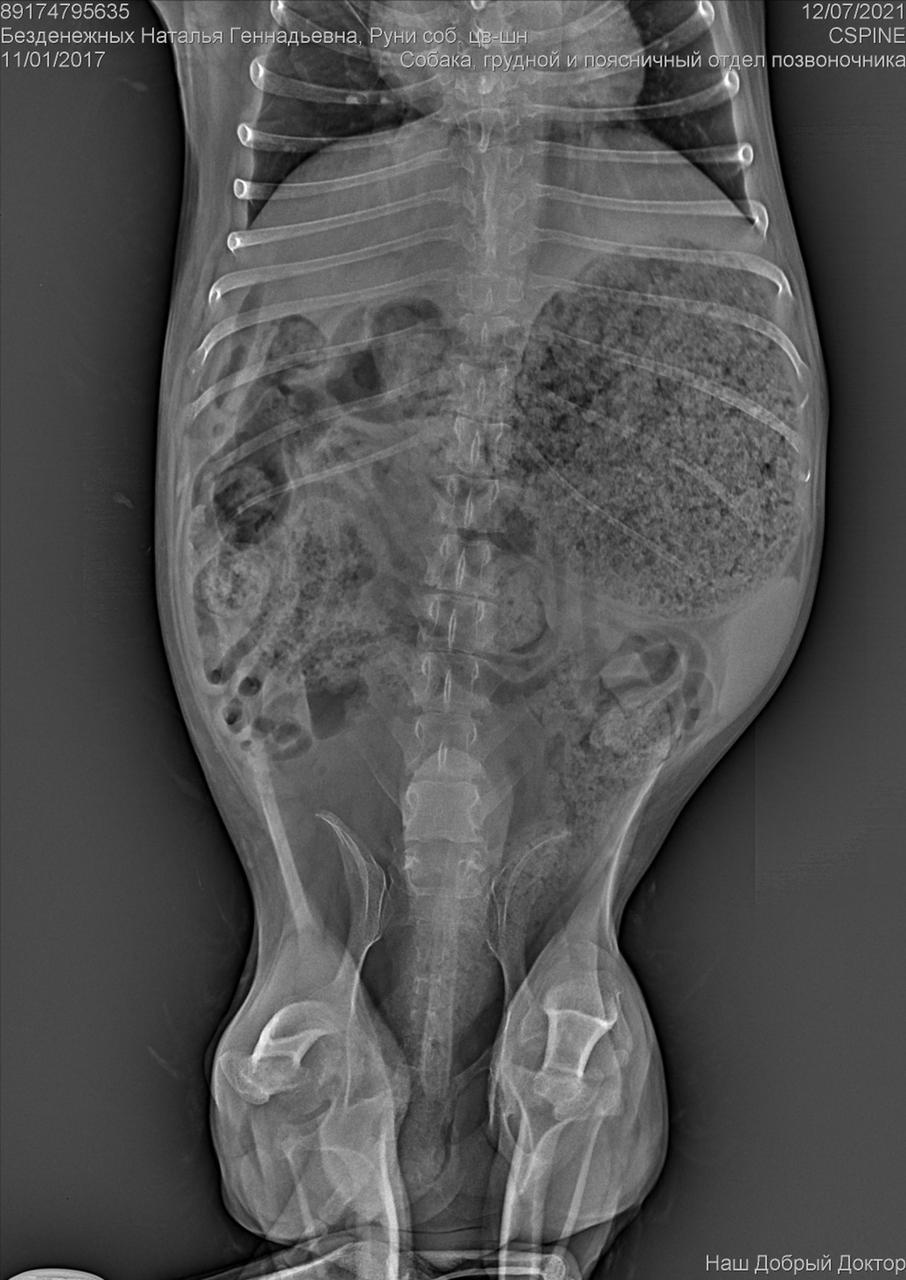

С собакой сегодня поедут в клинику. Передержать и полечить смогут. Попросила в клинике посмотреть клеймо и посканировать ип.

ПОнадобится наша помощь с оплатой лечения и поиском дома.